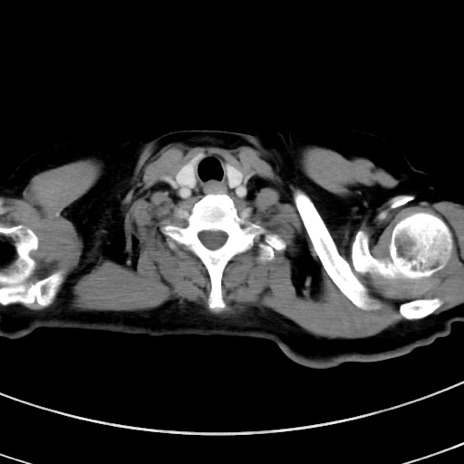

症例9(横断像)

【症例】 60歳代女性

【主訴】むかつき、みぞおちの痛み

【現病歴】3日前よりむかつきがあり、食事がとれない。

【既往歴】糖尿病

【身体所見】発熱なし、心窩部圧痛軽度あるも、腹膜刺激症状なし。

【データ】WBC 7400、CRP 1.92